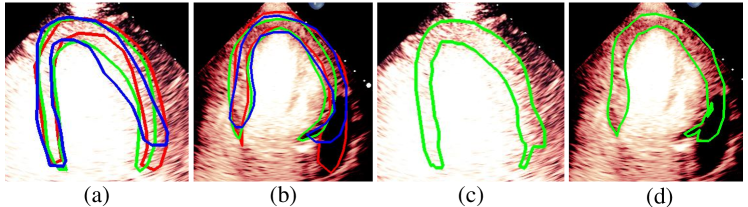

Visualization of myocardial segmentation from these methods is also shown in Fig. 4. We can see that for the Consensus, Confusion Matrix and Consistency methods, some unregulated shapes or discontinuity exist because the model cannot discriminate the actual myocardial from the artifacts which have the same intensity and texture information. However, the results of our method can alleviate the problem and accurately segment myocardium in MCE images.